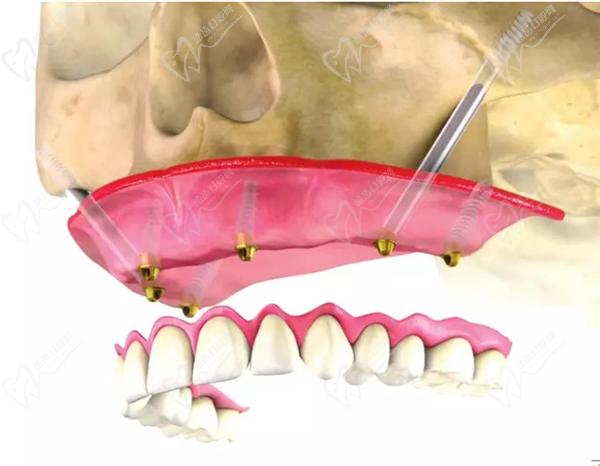

第三步:種植牙

接下來,醫(yī)生會在必要的位置上植入種植體。這些種植體充當(dāng)人工牙根,用于支撐和固定新的牙齒。采用數(shù)字化智能種植技術(shù),上下牙頜各僅需要4-6顆植體就能恢復(fù)半口牙14顆牙齒。

半口即刻負(fù)重種植牙流程圖